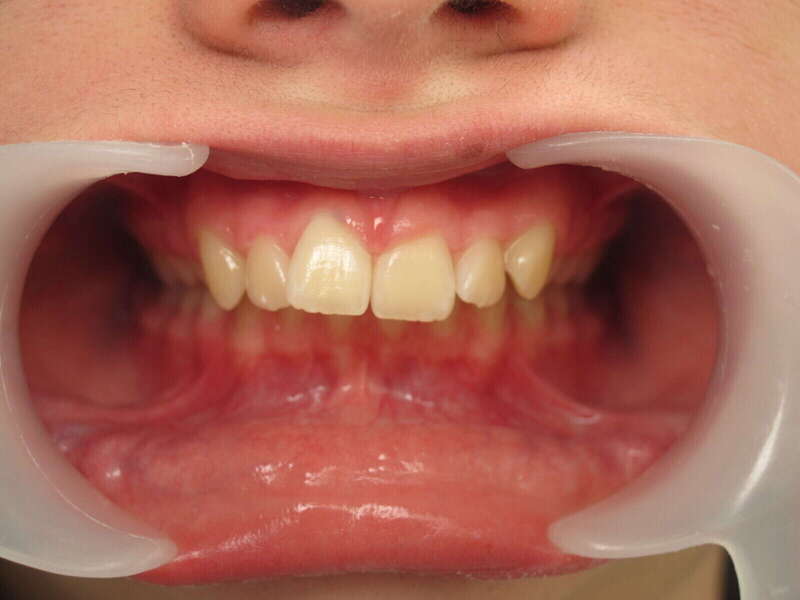

Cas n°1 traité par aligneurs (interception) - enfant

Ce cas d’interception chez un enfant de 8 ans démontre l'efficacité des aligneurs pour corriger des troubles fonctionnels précoces. Le diagnostic présentait des inversions d'articulé provoquant une déviation de la mandibule vers la gauche et un décalage des milieux.

Grâce à une coopération exemplaire et un traitement totalement indolore, l'expansion de l'arcade a permis de recentrer la mâchoire. Cette intervention a littéralement remis la croissance sur les rails, neutralisant le risque d'asymétrie faciale squelettique.

• Correction fonctionnelle : Recentrage immédiat de la mandibule et des milieux inter-incisifs.

• Prévention : Création d'un environnement favorable pour les dents définitives à venir.

• Bien-être : Approche douce respectant le confort de l'enfant.

C'est une étape fondamentale qui simplifie l'avenir orthodontique du patient tout en garantissant un développement facial harmonieux.